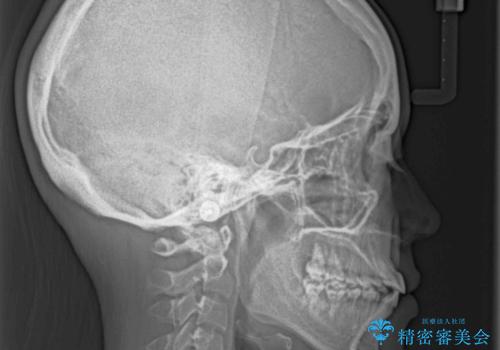

骨格的に下顎が前方位の受け口傾向であり、それが原因でクロスバイトとなっていました。

右奥の歯が180度回転していることで、噛む度にワイヤーに無理な力がかかったようで、頻繁にワイヤーが切れてしまいました。また、下顎を後方に移動させるためのアンカースクリューも脱離することが多く、治療期間が長くなってしまいました。